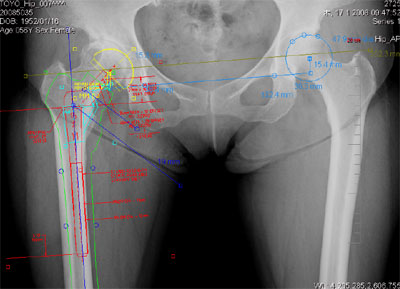

デジタルプランニングのイメージ

そこで,今回販売を開始する「OrthoPlanner Pro」では,骨折治療・人工関節手術のプランニングを画面上でデジタルに実施でき,かつX線撮影による患部データの拡大率の誤差を補正する機能※を実現した。

また,国内のユーザ(整形外科医)が本ツールを使用する際の作業効率の向上を念頭におき,国内外の主要インプラントメーカ13 社の人工関節テンプレートをデジタルテンプレートとして実装するとともに,プランニングにおける標準的な計測・作図方法をクリックのみで行えるようにするなどの機能を実現した。

- 正確な計測,テンプレーティングを実現するキャリブレーション(拡大率補正)機能